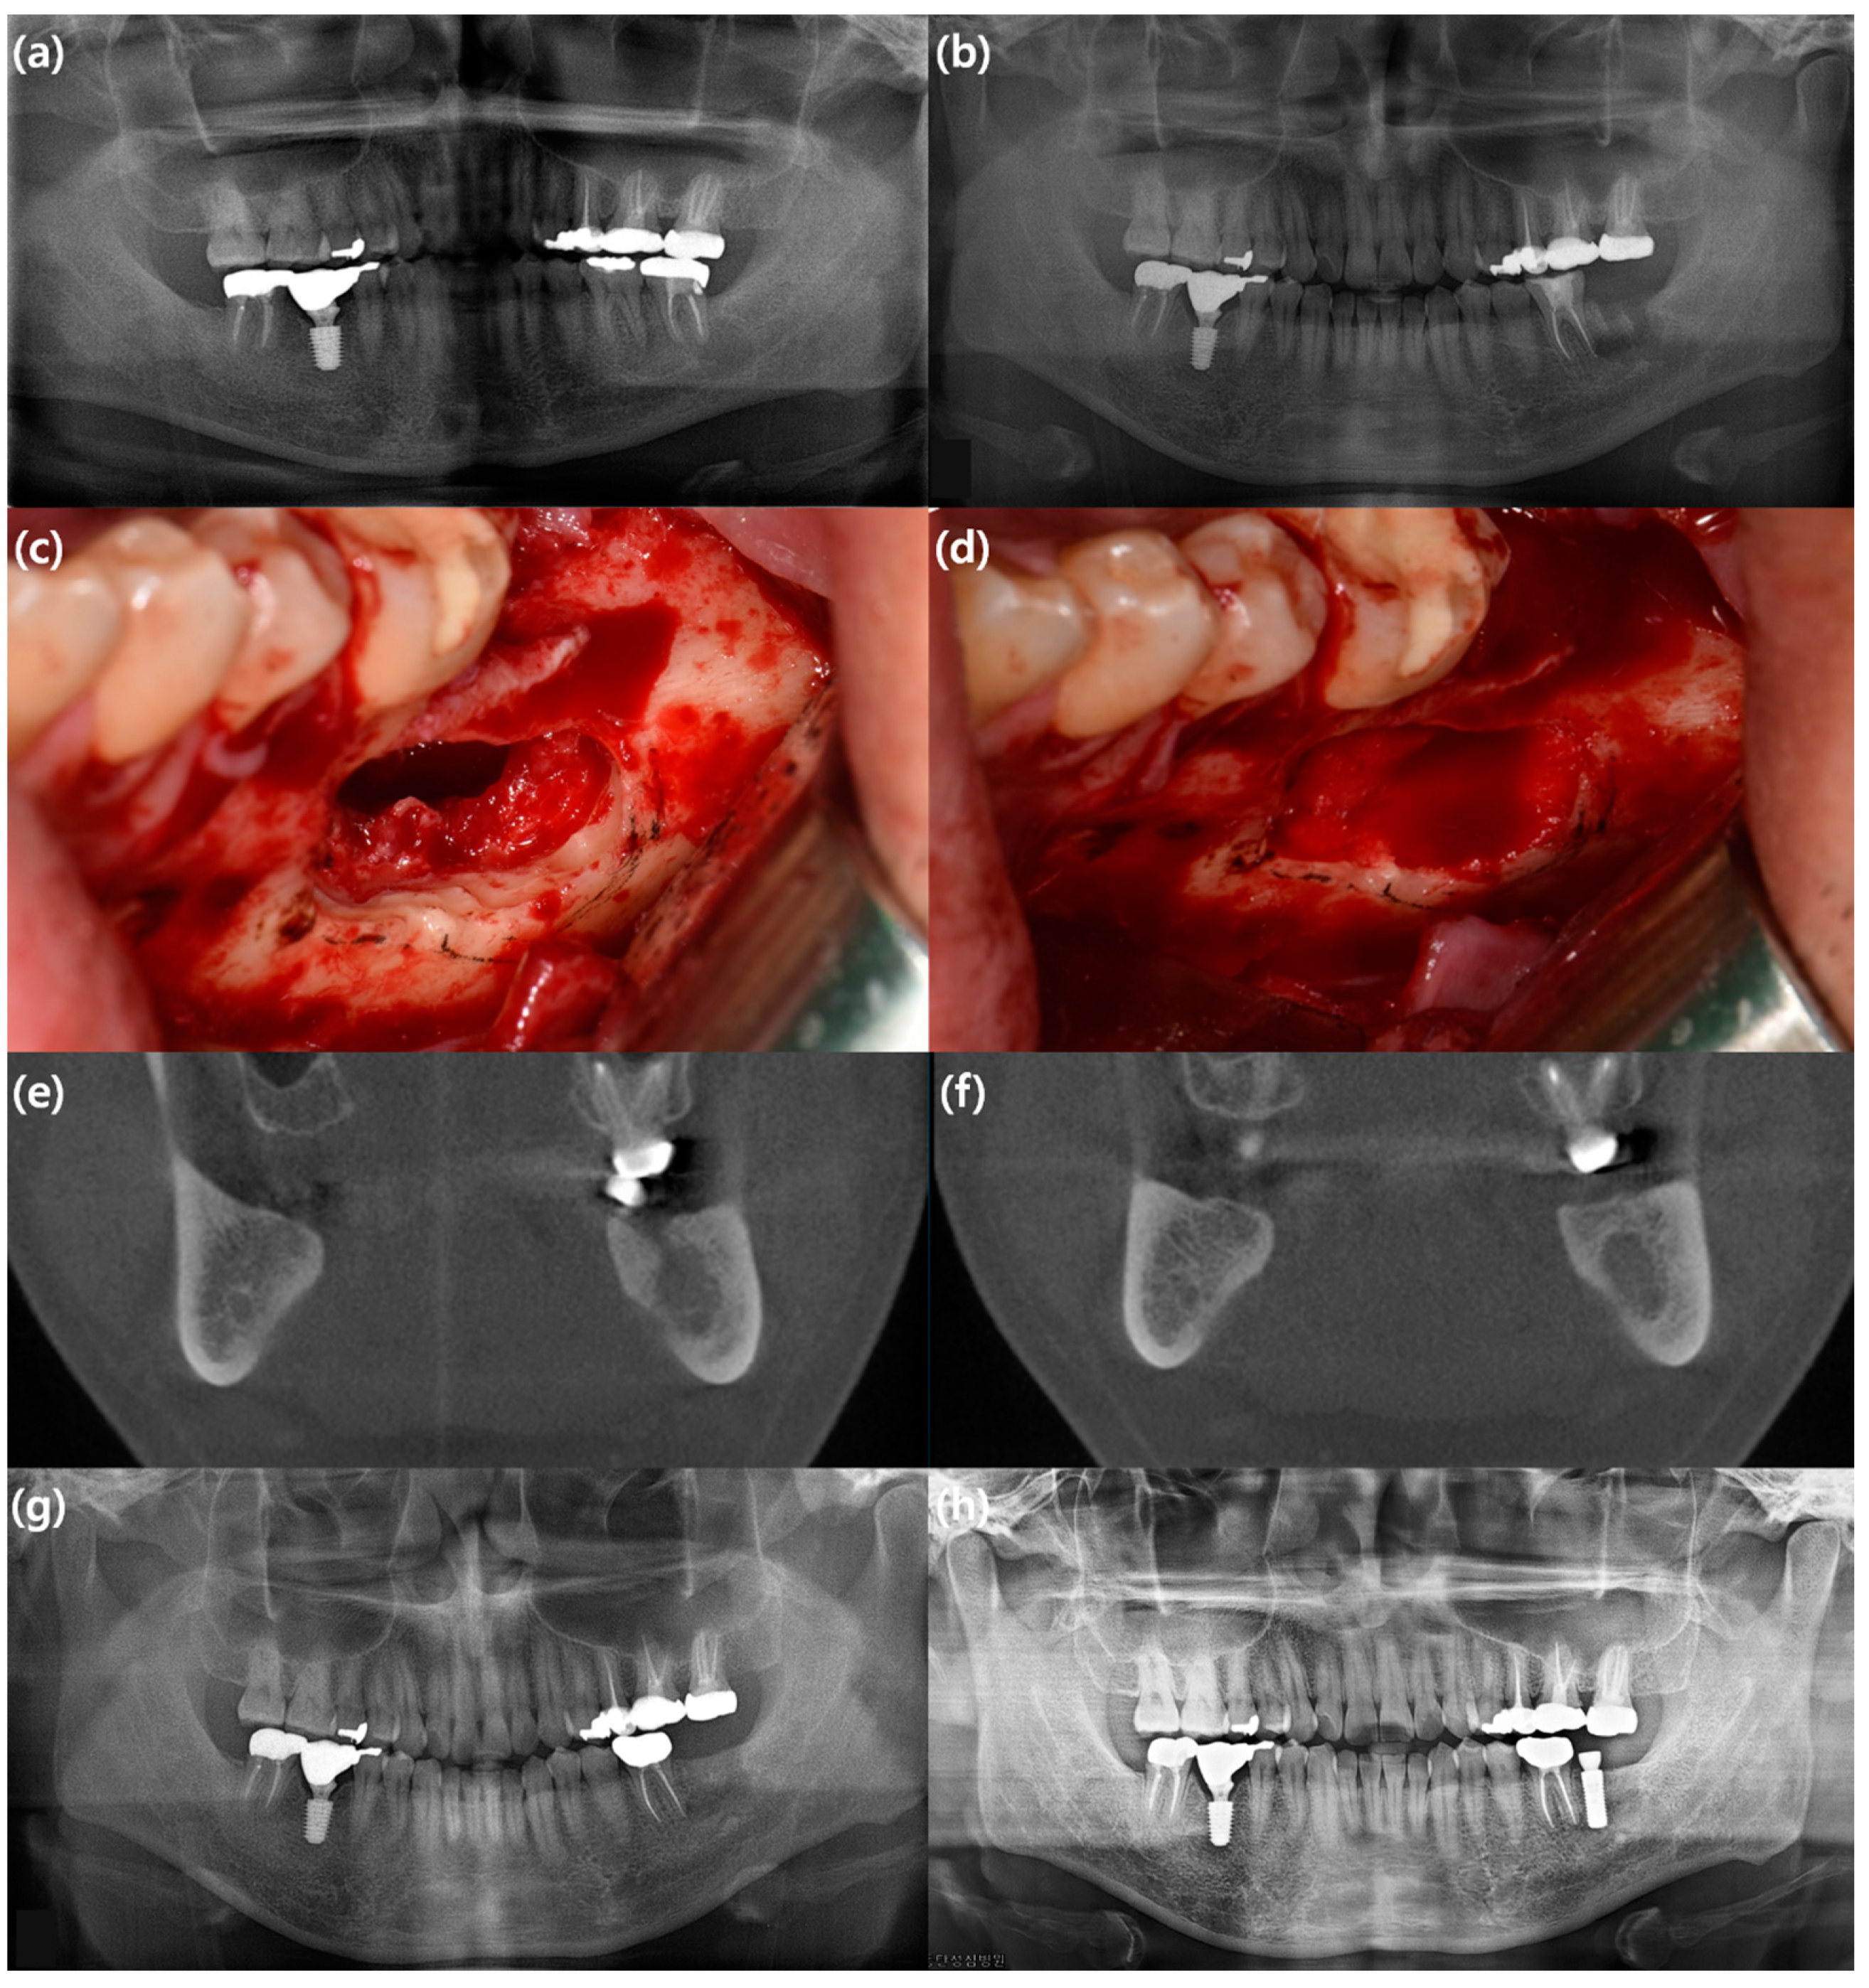

- Min, S.H.; Kang, N.E.; Song, S.I.; Lee, J.K. Regenerative effect of recombinant human bone morphogenetic protein-2/absorbable collagen sponge (rhBMP-2/ACS) after sequestrectomy of medication-related osteonecrosis of the jaw (MRONJ). J. Korean Assoc. Oral Maxillofac. Surg. 2020, 46, 191–196. [Google Scholar] [CrossRef]

- Park, J.H.; Kim, J.W.; Kim, S.J. Does the Addition of Bone Morphogenetic Protein 2 to Platelet-Rich Fibrin Improve Healing After Treatment for Medication-Related Osteonecrosis of the Jaw? J. Oral Maxillofac. Surg. Off. J. Am. Assoc. Oral Maxillofac. Surg. 2017, 75, 1176–1184. [Google Scholar] [CrossRef]